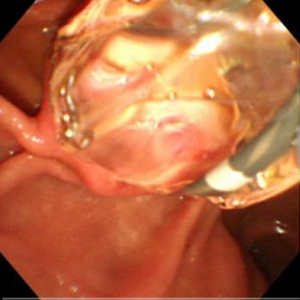

結石が胆管を閉塞し、胆管炎、閉塞性黄疸、急性膵炎などを発症します。緊急の処置が必要な場合が多く、放置すると命に係わる場合があります。通常バスケットカテーテルを用いて、結石を取り除きますが、石が大きい場合はESWL(体外衝撃波結石破砕術)を併用し排石する場合もあります。

ESWLとEST後large balloonによる乳頭拡張術を併用し完全排石に成功した巨大総胆管結石の一例